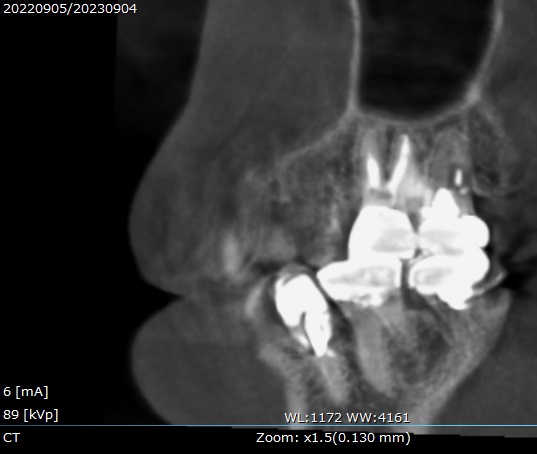

・治療1年後の状態

検診で来院された1年後に、新しくCTを撮影し状態を確認します。

1年後のCTの画像です。

正面からと、

横側からです☟

上顎洞の影が無くなっているのが分かります。

治療後のレントゲン写真では、根管にMTAセメントで充填してあり、

CTでは根の先まで白い詰め物がされているのが分かります。